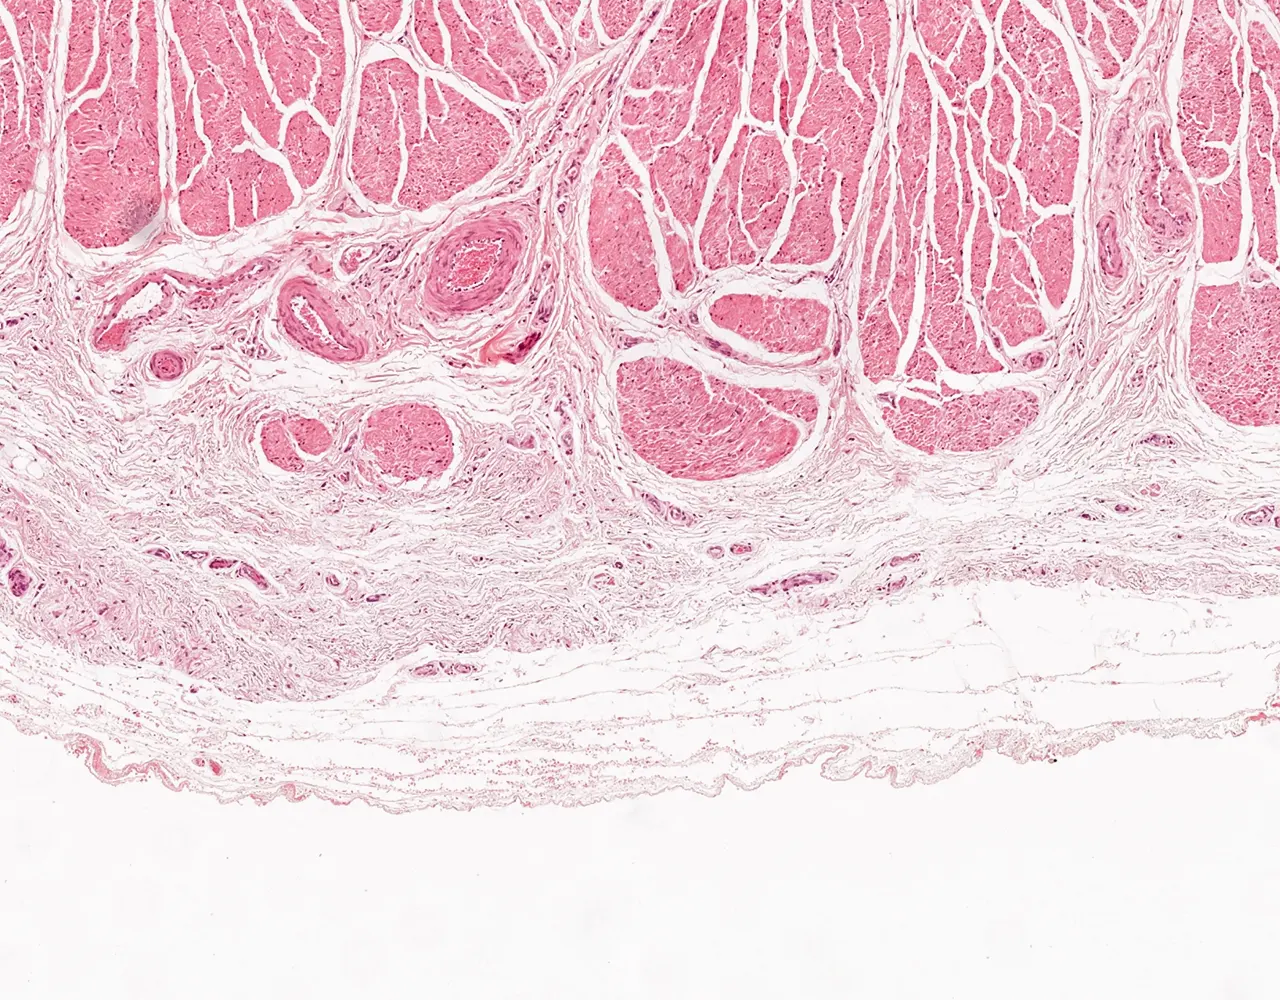

- Microscopically, the esophagus is composed of four layers: mucosa, submucosa, muscularis propria, and adventitia.